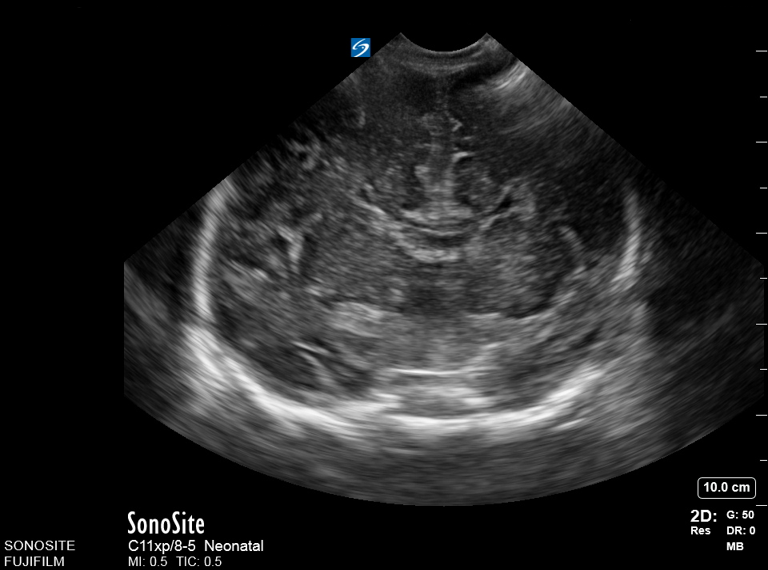

Neonatology Corpus Callosum Agenesis 3 Image